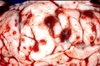

What kind of brain lesions due parasites usually create?

inflammatory and space occupying